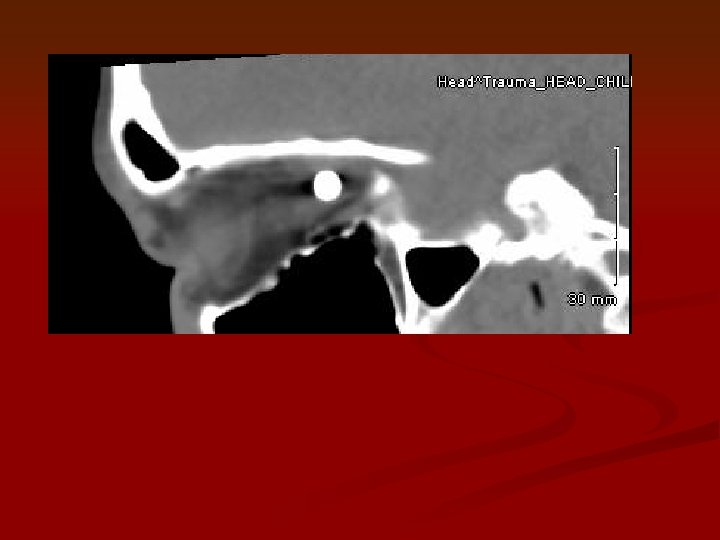

CT scan of orbit: BB pellet is within the right orbit in between the CT scan of orbit: BB pellet is within the right orbit in between the superior and medial rectus muscles in the superior medial aspect. It is superior and medial to the optic nerve.

Superior rectus BB Medial rectus Optic nerve CT scan of orbit: BB pellet is Superior rectus BB Medial rectus Optic nerve CT scan of orbit: BB pellet is within the right orbit in between the superior and medial rectus muscles in the superior medial aspect. It is superior and medial to the optic nerve.